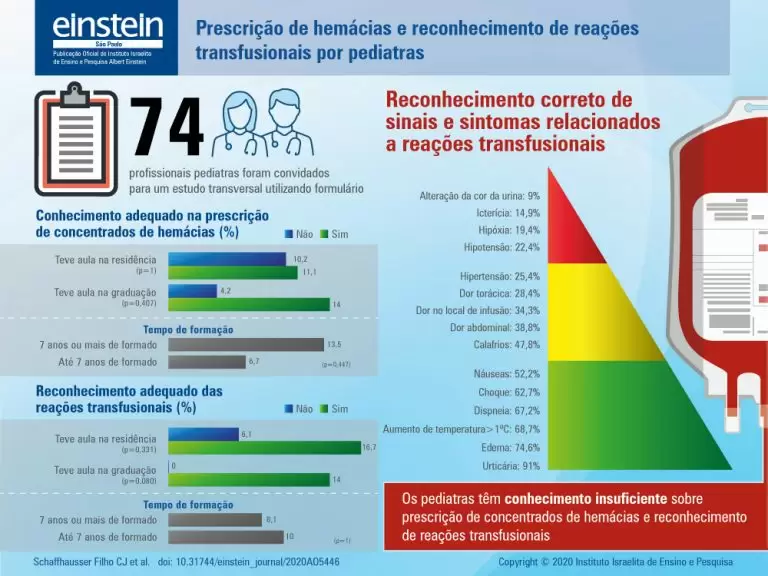

Prescrição de hemácias e reconhecimento de reações transfusionais por pediatras

DOI: 10.31744/einstein_journal/2020AO5446

RESUMO Objetivo Avaliar o conhecimento de pediatras emergencistas sobre transfusão de concentrados de hemácias e reações transfusionais. Métodos Aplicação de formulário para pediatras emergencistas de um hospital pediátrico. Resultados Menos de 20% dos participantes demonstraram conhecimento adequado sobre prescrição de concentrados de hemácias e reconhecimento de reações transfusionais. Não houve diferença estatística significativa quando avaliados o tempo de formação profissional e o fato de ter recebido aula de hemoterapia na graduação ou na residência médica. Conclusão Os pediatras têm conhecimento […]

Palavras-chave: Criança; Crianças; Educação médica; Medicina transfusional; Reação transfusional; Transfusão de eritrócitos